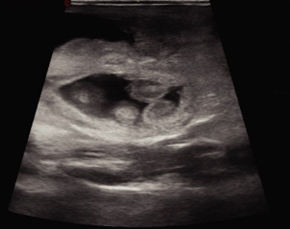

Imágenes Clínicas